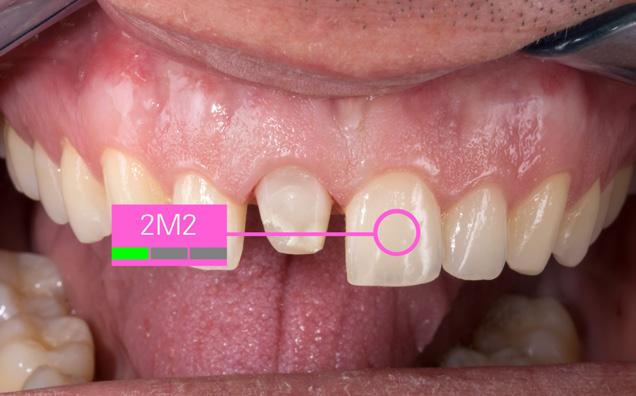

independently from the ambient conditions and the tooth shade was determined. This procedure was used to determine the 2M2 tooth shade for the patient and to select the systemrecommended VITABLOCS RealLife blank (VITA Zahnfabrik, Bad Säckingen, Germany). In order to provide the dental technician with detailed information on the results, additional digital photos were created in RAW format. The photographs were taken using the shade guide and a polarizing filter in order to reduce reflections.

A patient’s upper middle incisor was reconstructed using a direct composite restoration, which fractured. In addition to the material deficiency, the patient was also not satisfied with the tooth shade and aesthetic appearance. For that reason, the decision was made to reconstruct the tooth using an efficient, digital workflow with a monolithic, tooth-coloured feldspar ceramic crown. In order to treat the patient in a single session, a full crown restoration was performed and the composite structure was almost entirely removed. Following that, a temporary crown was made from the CAD/CAM VITA CAD-Temp multiColor composite material using the 2M2 shade, in order to stabilize the tooth and soft tissue.

Tooth shade determination

The shade was digitally determined using the VITA Easyshade V, which achieved a perfect colour match between the new restoration and the neighbouring left incisor tooth. A spectrophotometer was used to transmit defined light into the dentine core and the reflected light spectrum was recorded by a measuring probe. The spectral data was then analysed

Fig. 1: The insufficient, fractured composite filling on tooth 11 was to be restored using a CAD/CAM-supported feldspar ceramic crown.

Fig. 5: The basic shade 2M2 was determined using the VITA Easyshade V.

Fig. 7: Since the shade of the prepared tooth affects the shade of the restoration, a three-point measurement was conducted.

Fig. 2: As a quick solution, a temporary composite crown was fabricated using CAD/ CAM-based VITA CAD-Temp multiColor.

4: During the preparation, the minimum layer thickness of the restoration was observed.

6: The shade of the adjacent tooth was integrated into a digital photo and sent to the laboratory.

Fig. 8: A digital photograph with polarizing filter and corresponding shade tabs provided the dental technician with individualized information.